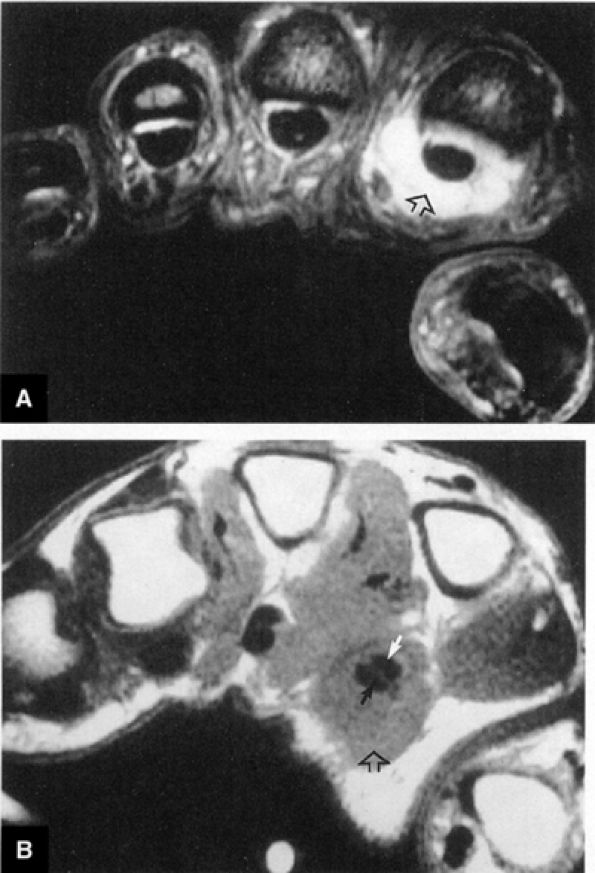

![]() |

FIGURE 10.3 ● Identification of the dorsal fibers of the scapholunate and lunotriquetral ligaments on a coronal T1-weighted arthrogram. Although MR arthrography is frequently performed with FS, this decreases signal-to-noise. Routine FS PD FSE sequences are still used when performing MR arthrography, usually in the coronal and axial planes, to evaluate muscle and tendon pathology, chondral abnormalities, subchondral marrow edema, and noncommunicating ganglions. Postarthrogram sequences limited to FS T1-weighted sequences alone are inadequate for comprehensive diagnostic assessment.